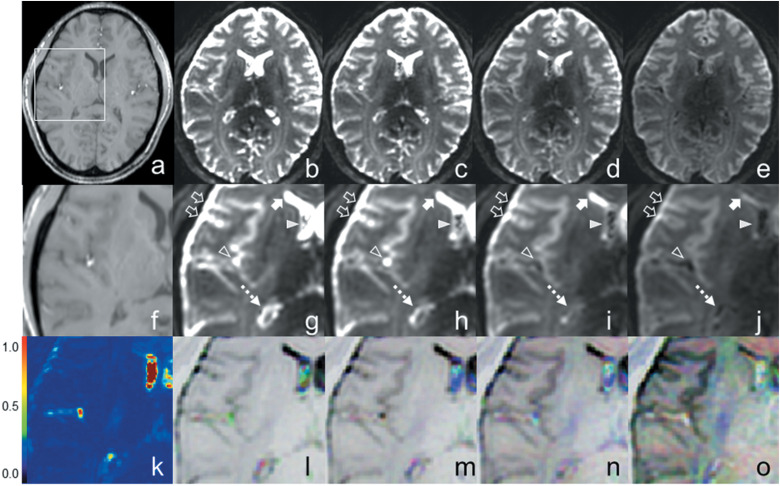

Purpose: The present study aimed to investigate whether diffusion-weighted imaging (DWI) can qualify and quantify cerebrospinal fluid (CSF) dynamics in the brains of healthy subjects. For this purpose, we developed new DWI-based fluidography and compared the CSF dynamics seen on the fluidography with two apparent diffusion coefficients obtained with different DWI signal models at anatomical spaces filled by CSF.

Methods: DWI with multiple b values was performed for 10 subjects using a 7T MRI scanner. DWI-fluidography based on the DWI signal variations in different motion probing gradient directions was developed for visualizing the CSF dynamics voxel-by-voxel. DWI signals were measured using an ROI in the representative CSF-filled anatomical spaces in the brain. For the multiple DWI signals, the mono-exponential and kurtosis models were fitted and two kinds of apparent diffusion coefficients (ADCC and ADCK) were estimated in each space using the Gaussian and non-Gaussian diffusion models, respectively.

Results: DWI-fluidography could qualitatively represent the features of CSF dynamics in each anatomical space. ADCs indicated that the motions at the foramen of Monro, the cistern of the velum interpositum, the quadrigeminal cistern, the Sylvian cisterns, and the fourth ventricle were more drastic than those at the subarachnoid space and anterior horns of the lateral ventricle. Those results seen in ADCs were identical to the findings on DWI-fluidography.

Conclusion: DWI-fluidography based on the features of DWI signals could show differences of CSF dynamics among anatomical spaces.